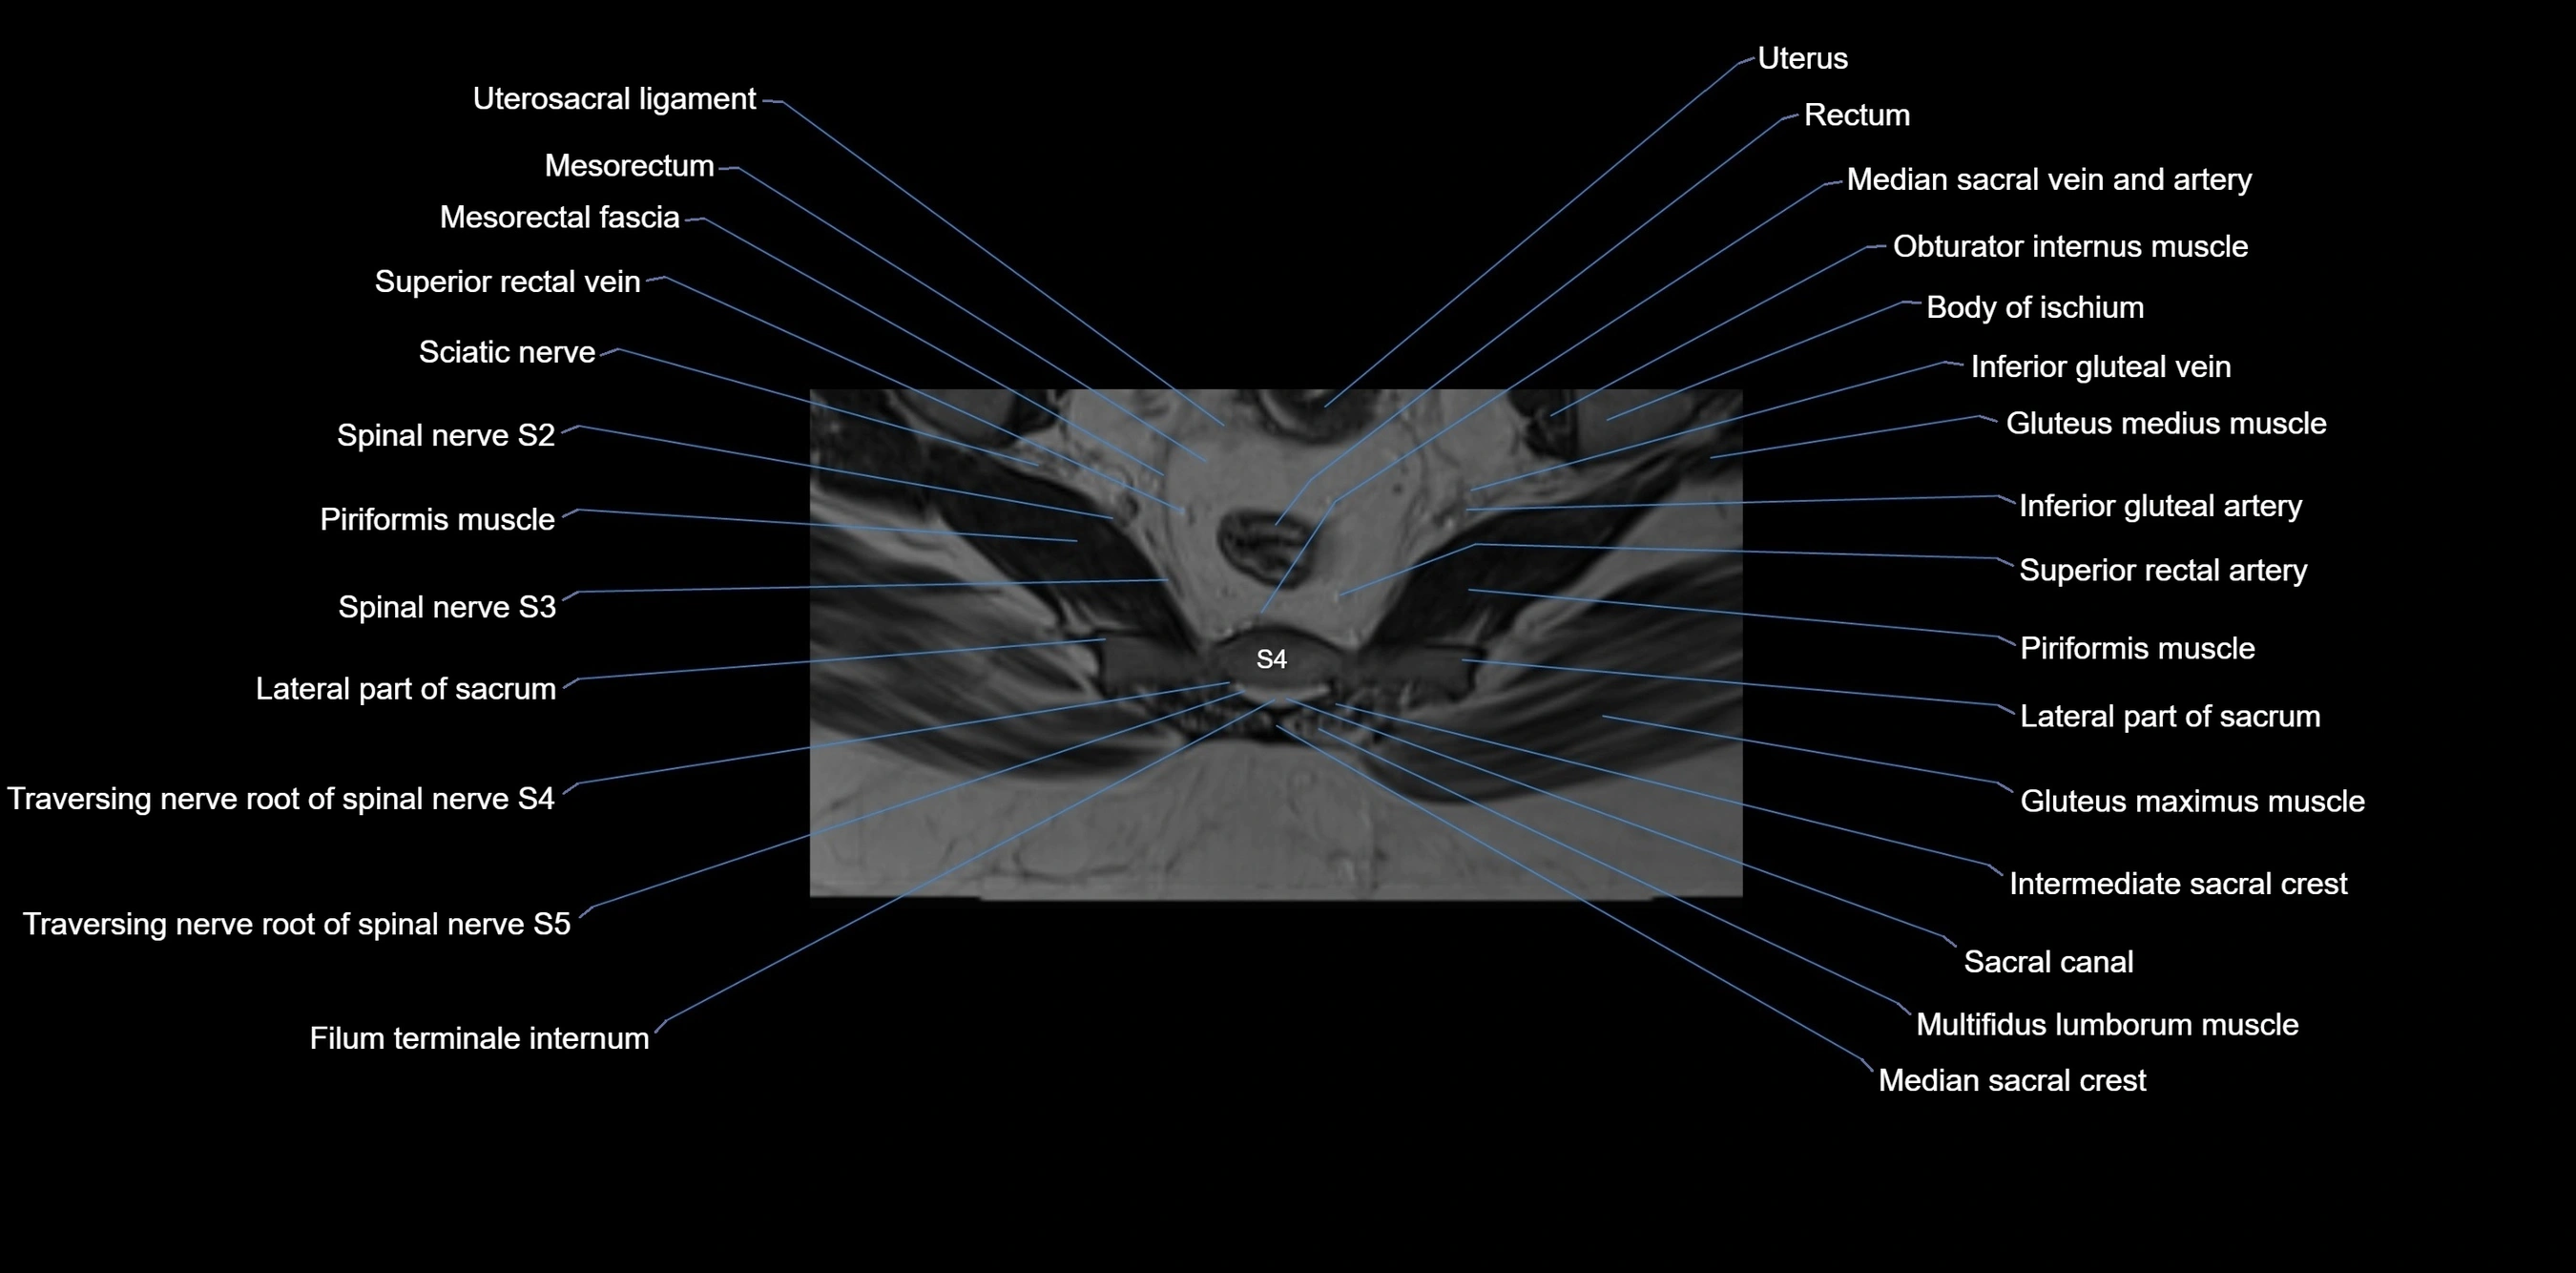

MRI image

image